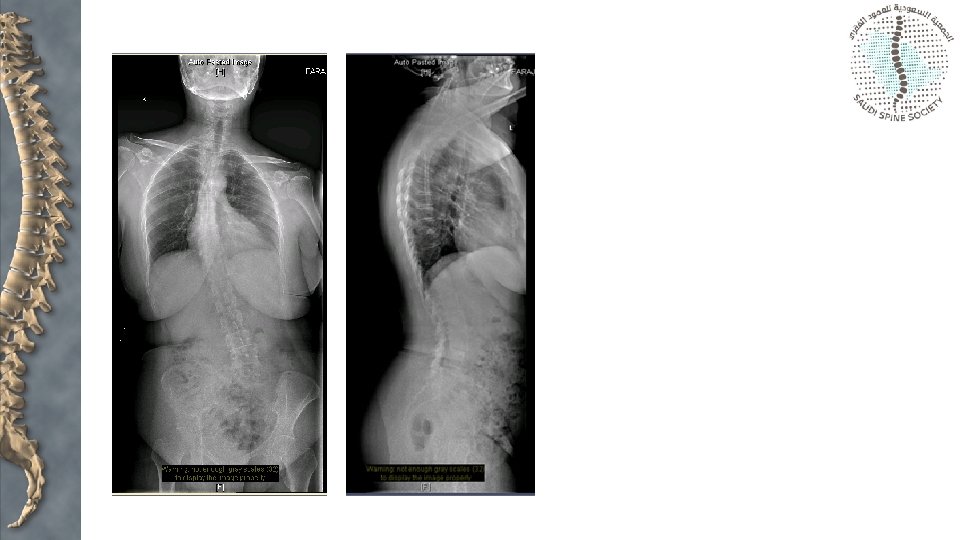

Sagittal alignment • Stance • Gait • Head over pelvis • Hips and knees

Measurement • Pelvic incidence • • • PI = PT + SS Mean children 47 degrees Mean adults 57 degrees Low PI loss of lordosis High exaggerated lordosis

Low PT High SS High PT Low SS

Risk factors for progression • • • Young age (progression is rare after 20 years) Female Ligamentous laxicity > 50% slippage > 10% slip angle L 5 - S 1 instability Trapeaoidal L 5 Dome- shaped upper sacrum Less likely to progress with decreased disk space and an Anterior sacral lip